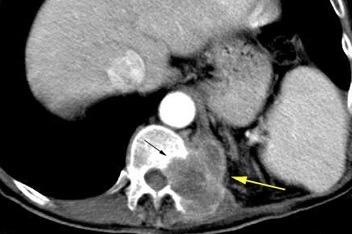

Nódulos pulmonares múltiples. (flechas verdes). Masas paratraqueales. (flechas amarillas). Dudoso ensanchamiento retrocrural (flechas negras). sigue….

Ttawfik A et al. Trans-diaphragmatic Pathologies: Anatomical Background and Spread of Disease on cross-sectional Imaging. Current Problems in Diagnostic Radiology. 2021.

T. mixto de células germinales del testículo

izquierdo Metástasis pulmonares. (flechas verdes). Ganglios paratraqueales. (flechas amarillas). Ganglios retroperitoneales (flechas negras)

Tawfik A et al. Trans-diaphragmatic Pathologies: Anatomical Background and Spread of Disease on cross-sectional Imaging. Current Problems in Diagnostic Radiology. 2021.